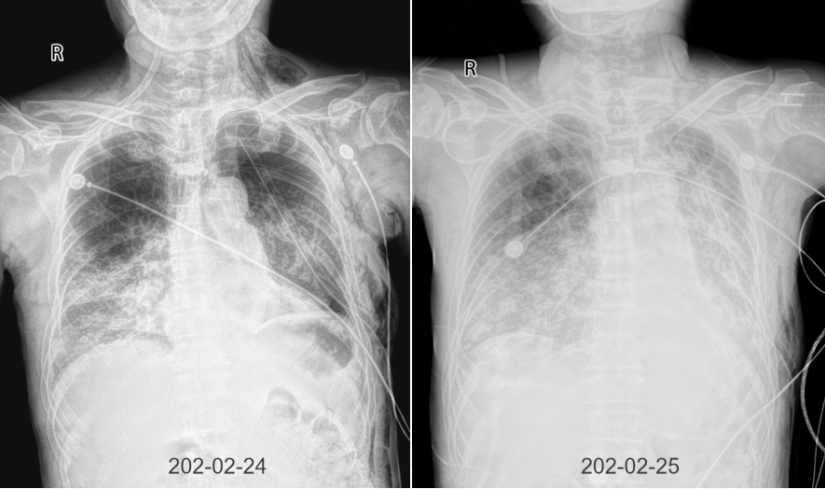

3月24日调整抗感染治疗,改为多西环素+头孢他啶抗感染治疗。3月31日复查胸部CT较前好转,间断脱机行呼吸功能锻炼。复查患者感染指标整体呈下降趋势,脏器功能指标得到一定程度的改善(表6)

3月31日复查胸部CT:双肺多发斑片影,左肺下叶切除术后,左侧少量胸腔积液,纵隔淋巴结肿大(图6)

6  复查胸部CT(2024-03-31)

积极行呼吸康复锻炼,4月3日气管切开套管接经鼻高流量湿化氧疗。4月7日拔除气管切开套管转普通科室继续治疗。4月20日复查胸片,可见病变较前明显吸收(图7)

7  患者胸片变化情况